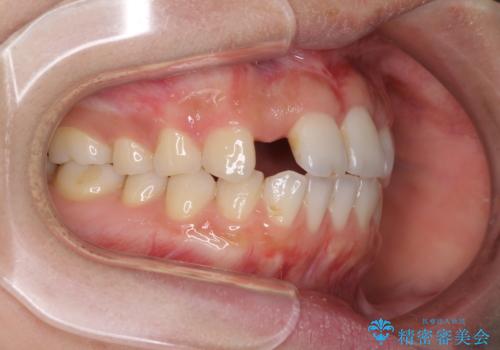

欠損歯と矮小歯 矯正治療と前歯のセラミック治療

- 前歯の隙間を気にして来院された患者様です。

診察の結果、前歯が1本欠損しており、さらに矮小歯(通常よりも小さい歯)が1本存在していました。

欠損による前歯のスペースが大きかったため、事前にワイヤー矯正で前歯の位置を大きく動かし、その後は上下をインビザラインで整えることとしました。

矯正治療後には欠損部はオールセラミックブリッジに、矮小歯はオールセラミッククラウンにて補綴することとしました。